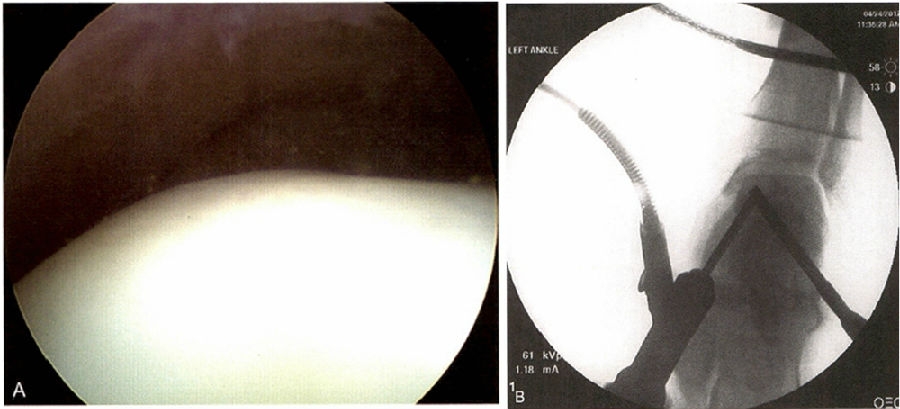

软骨下骨囊性变而软骨表面完整的病例适合采用逆行钻孔并结合植骨的治疗方法。通过空心钻进行逆行钻孔,能够对囊性病变进行彻底清理,并植入自体松质骨进行填充,使损伤区域获得良好的愈合,并且具有不破坏关节软骨面的优点。近来,一些学者报道钻孔后在骨道内注射液体硫酸钙,另一些学者从髂骨采集骨髓,分离提纯骨髓干细胞,与液体钙混合后注射于局部缺损区域,有利于促进骨软骨的快速修复。

无论在开放手术还是在关节镜手术中,目前最佳的技术还是对关节缺损面的清创和钻孔。经踝钻孔(近端至远端钻孔)可以通过关节镜监视或经皮增强造影检查辅助完成。胫骨远端骨骺未闭合时要避免穿骺板的多次钻孔。